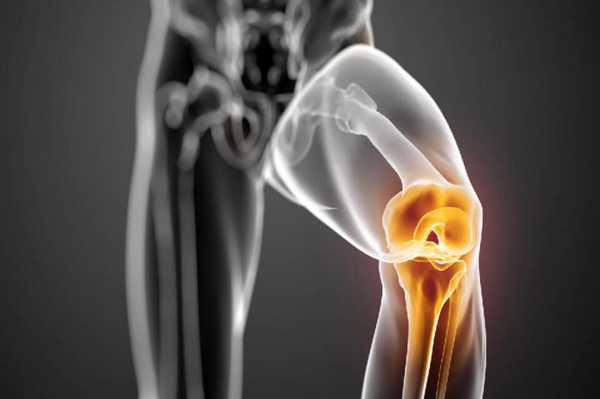

Костно-хрящевые структуры колена, приводящие в движение коленный сустав и отвечающие за опороспособность конечностей, - это самые уязвимые анатомические компоненты, которые поражаются артрозами. Эндопротезирование эффективный способом восстановления опорно-двигательного аппарата, которая подверглась серьезной дегенеративно-дистрофической агрессии на фоне хронического артроза.

Динамика разрушения хрящевой поверхности.

Макет импланта коленного сустава.